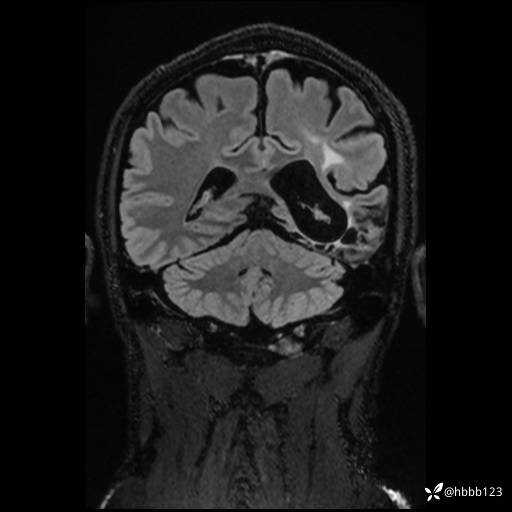

CUBE FLAIR冠状位: